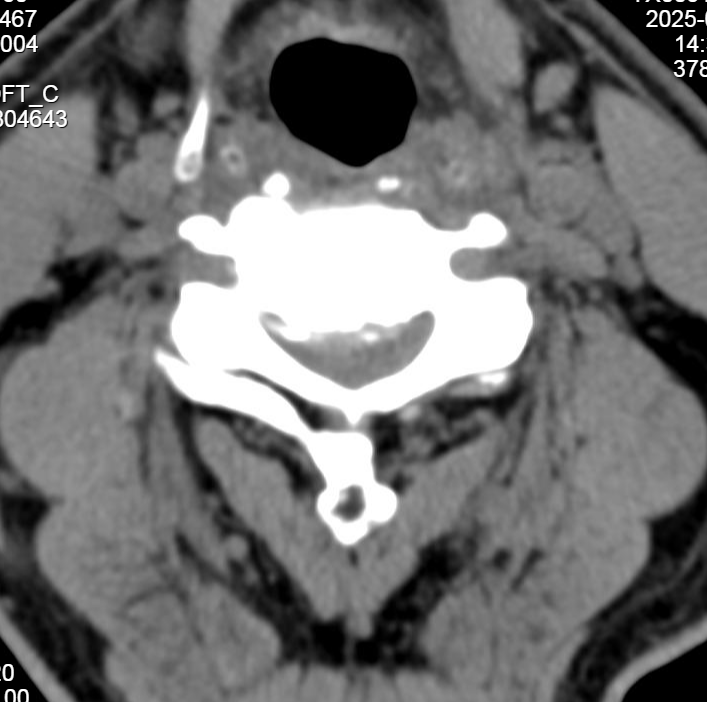

最终被确诊为

“颈椎后纵韧带骨化症(OPLL)合并

脊髓损伤、颈椎管狭窄及滑脱”

即在滑脱节段实施椎板切除减压内固定术

同时在OPLL节段进行单开门椎管扩大成形术